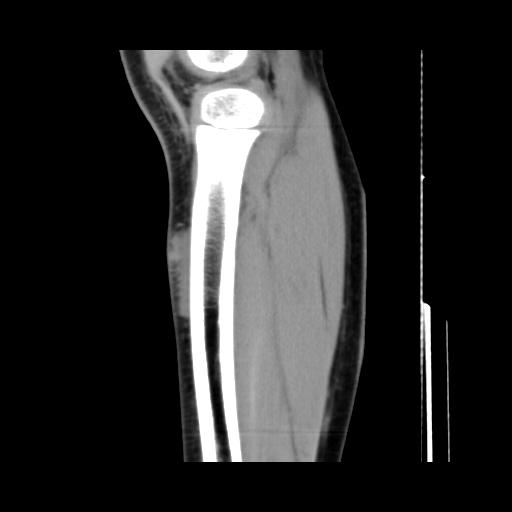

标题: PED0931:男,5岁,发现双小腿软组织肿块1年,质地中等,无 [打印本页]

标题: PED0931:男,5岁,发现双小腿软组织肿块1年,质地中等,无

多发性神经纤维瘤?

考虑多发性神经纤维瘤.